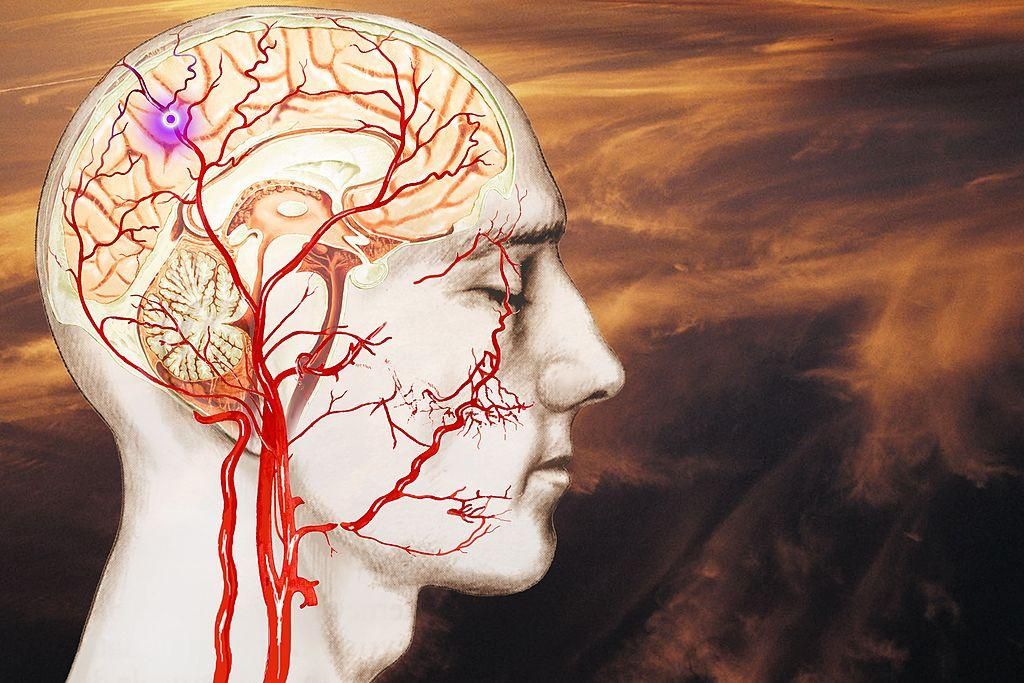

Il cervello è l’organo più complesso e meraviglioso del nostro corpo. Tuttavia, è una struttura misteriosa ed è avvolta da numerosi equivoci e bufale.